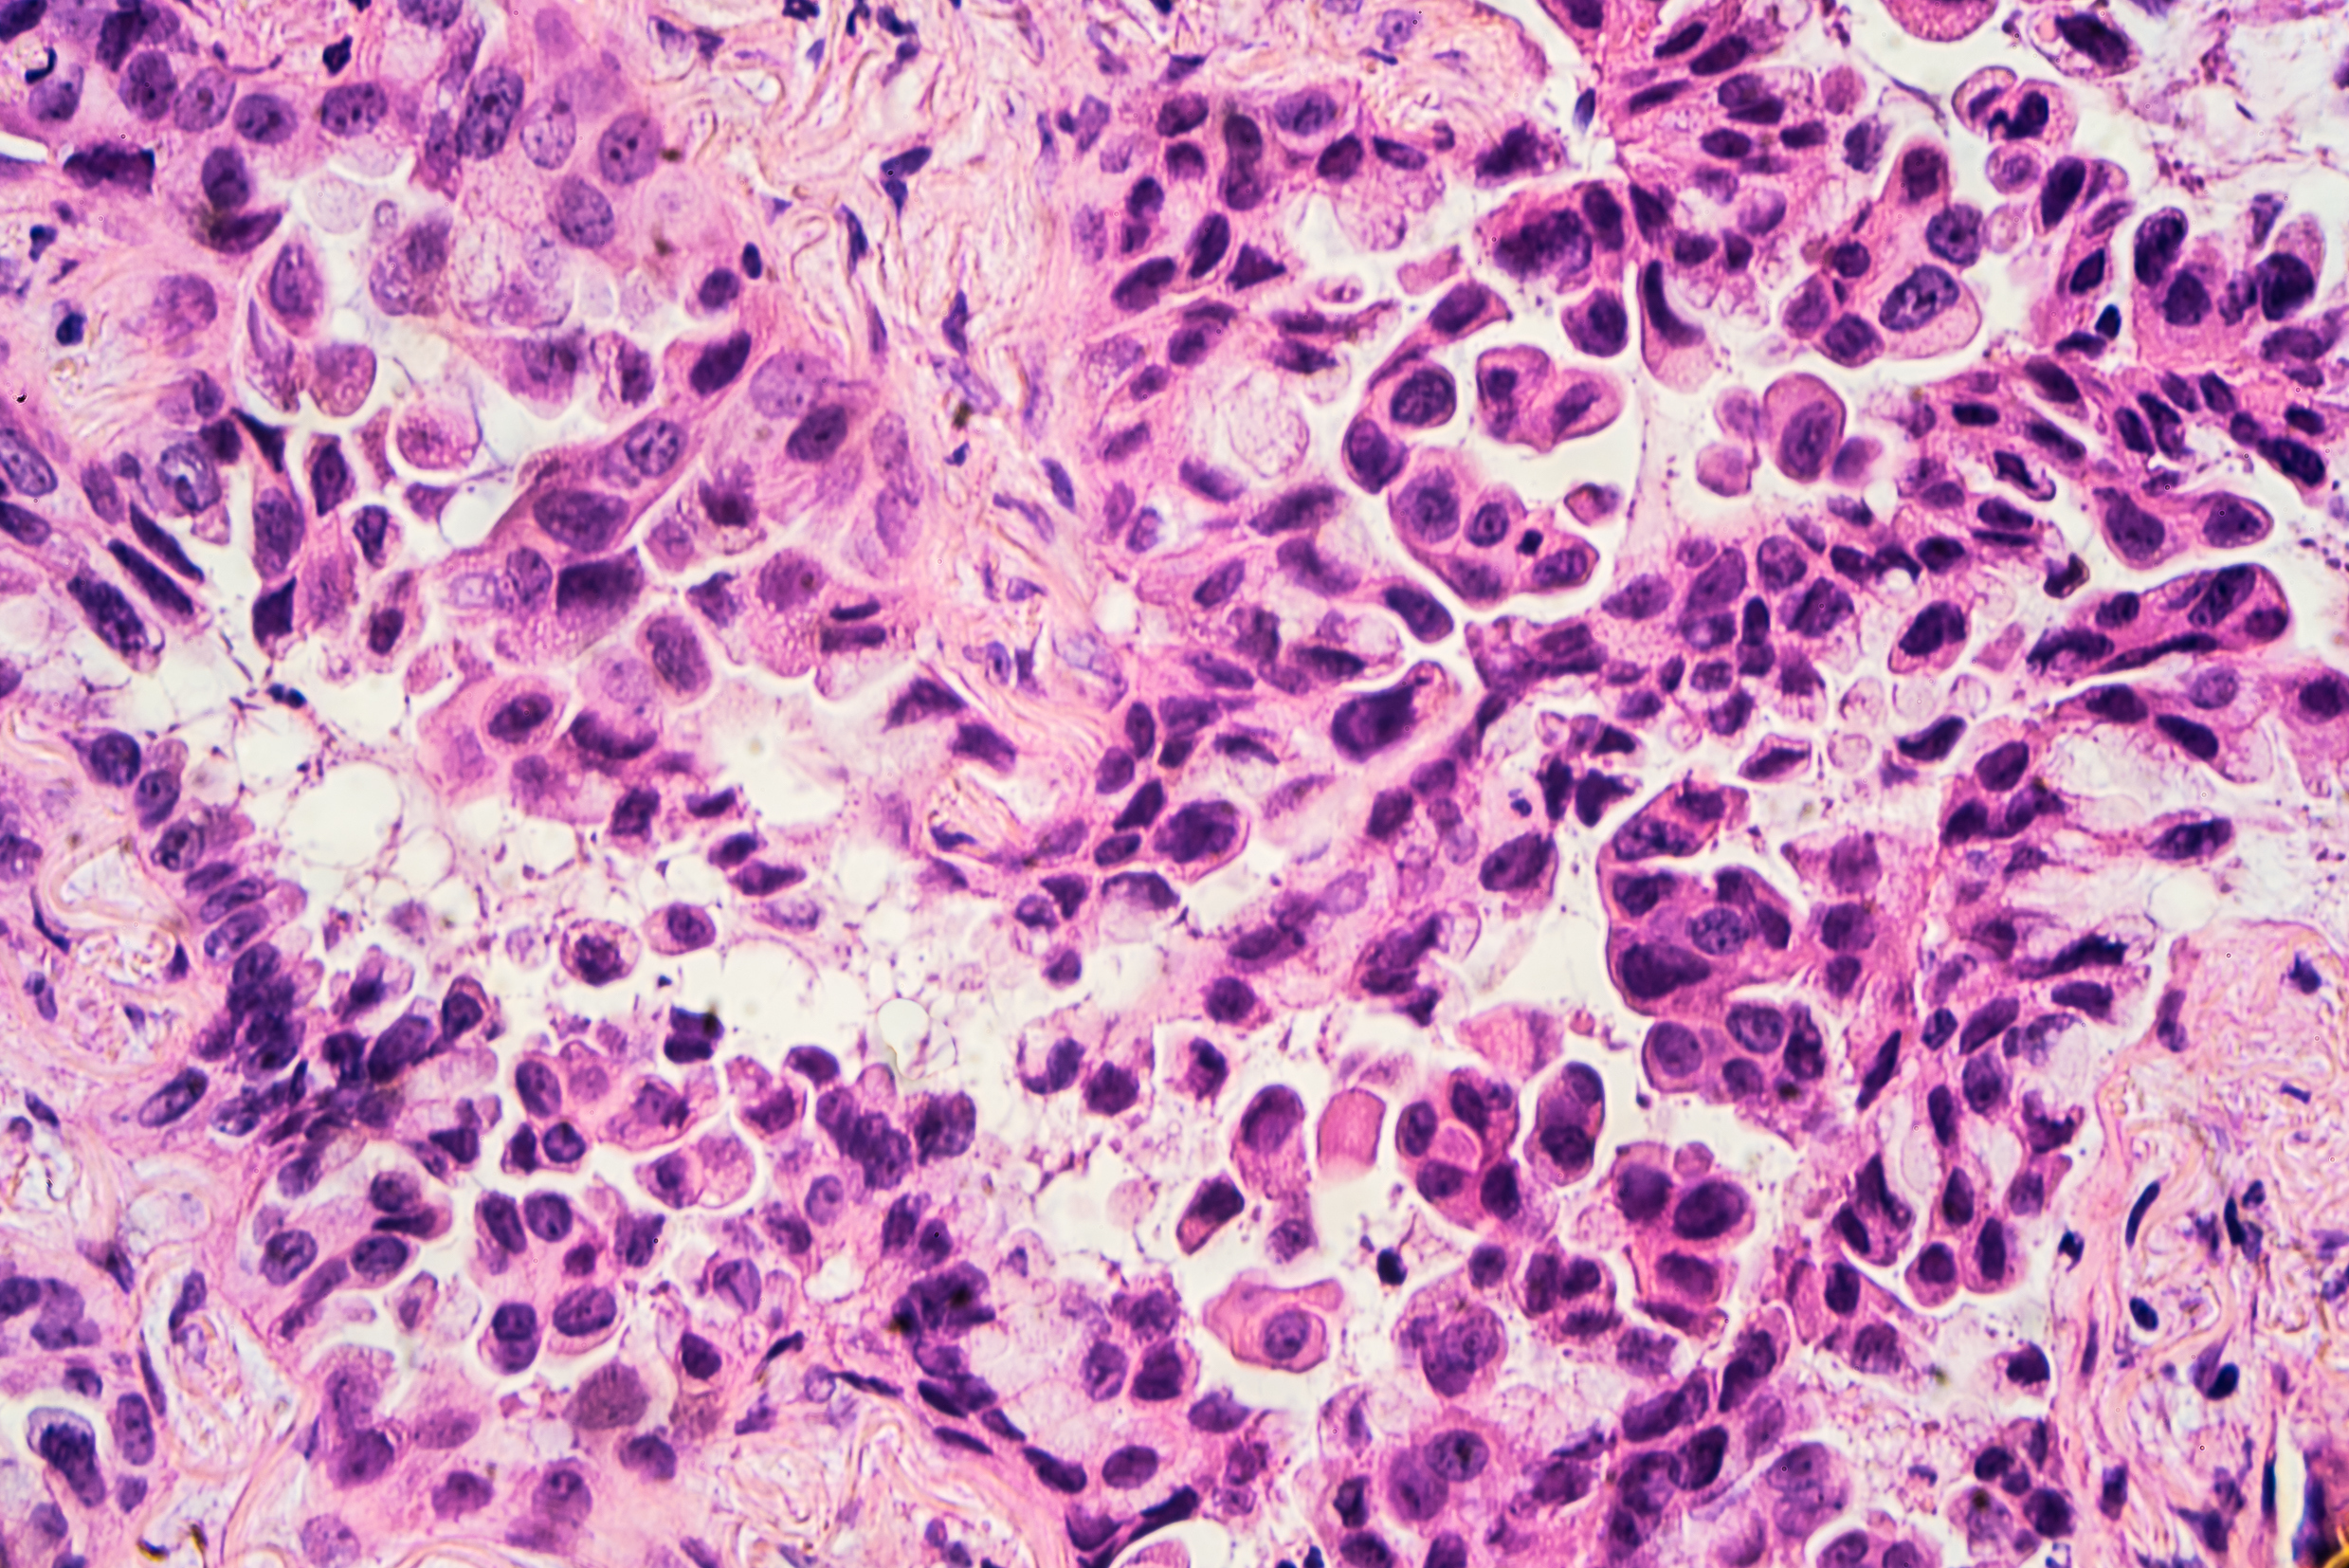

Гистологический срез плоскоклеточного рака — одного из подтипов немелкоклеточного рака легкого

Изображение: librepathology.org

Рак легкого делится на типы в зависимости от того, как выглядят вышедшие из-под контроля клетки и какого они размера. Самый распространенный тип — немелкоклеточный рак легкого, который составляет примерно 85 процентов от всех случаев рака легкого.